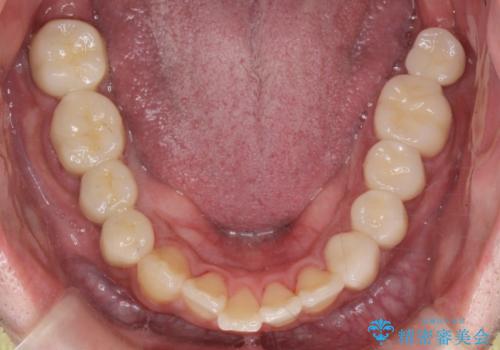

その後、インプラント治療、セラミック治療を行いました。

一度治療するはを全て仮歯に変えて、歯茎を整えてからセラミックを装着しました。

適合の良い被せ物、インプラントが入りました。